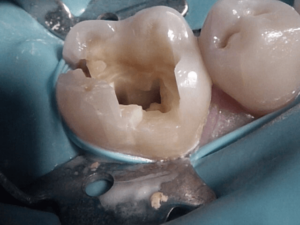

Before and After Treatments

Gordon Street Dental Success Stories in Guelph

Many Patients have allowed us to show what we’ve done for them. Please feel free to look at what we’ve done for them, as well as envision what we can do for you.

Image Grid Title

As a family dentist in Guelph, Dr. Lansdell is proud to provide comprehensive Dental Exams, Dental Cleanings, Fillings, beautiful Dental Crowns, Dental Bridges, Dental Implant Crowns, Emergency Dental Care, Laser Gum treatments, Invisalign, Teeth Whitening and so much more!